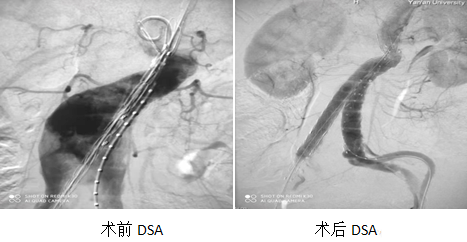

患者53歲男性,主因“發(fā)現(xiàn)腹主動脈瘤7月,下肢跛行3月。”入院,患者半年前復(fù)現(xiàn)腹主動脈瘤,未進(jìn)行規(guī)范化治療,近3月來出現(xiàn)右下肢間歇性跛行。既往無高血壓病、糖尿病、高血脂等危險(xiǎn)因素。患者7月前發(fā)現(xiàn)腹主動脈瘤,右側(cè)股動脈通暢;入院檢查提示腹主動脈瘤伴附壁血栓,雙髂動脈瘤,雙股動脈瘤,右股淺動脈閉塞,結(jié)合病史考慮右下肢為附壁血栓脫落引起右下肢動脈栓塞;因此患者需一期行腹主動脈瘤腔內(nèi)隔絕術(shù),二期行右下肢手術(shù)動脈腔內(nèi)成形術(shù)。

經(jīng)多學(xué)科討論后決定行雜交手術(shù)治療,介入組負(fù)責(zé)腹主動脈瘤覆膜支架置入;外科組負(fù)責(zé)雙側(cè)股動脈切開、雙側(cè)股動脈瘤折疊縫合成形術(shù)。經(jīng)積極術(shù)前準(zhǔn)備,并向醫(yī)務(wù)部報(bào)重大手術(shù)計(jì)劃后于2021.11.24日順利完成我院首例雜交手術(shù),雜交手術(shù)的進(jìn)行規(guī)避了內(nèi)外科手術(shù)治療的各自風(fēng)險(xiǎn),不但有介入手術(shù)創(chuàng)傷小,術(shù)后恢復(fù)快優(yōu)勢,又充分解決了股動脈瘤(介入入路)破裂、出血風(fēng)險(xiǎn)。

對于主動脈疾病,傳統(tǒng)手術(shù)是開胸、開腹建立體外循環(huán)后進(jìn)行血管重建,創(chuàng)傷大、失血多、術(shù)后感染等風(fēng)險(xiǎn)大,介入聯(lián)合外科手術(shù)治療降低了手術(shù)風(fēng)險(xiǎn)、麻醉風(fēng)險(xiǎn)等,并且術(shù)后恢復(fù)快。雜交手術(shù)的開展預(yù)示著我院心血管病治療領(lǐng)域又向國內(nèi)、國際先進(jìn)水平邁進(jìn)一步。